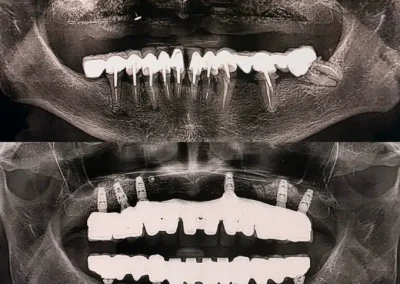

Your treatment begins with a complete evaluation using 3D scans and digital imaging. This allows our specialists to locate bone loss, measure bone density, and plan a graft suited to your needs. We perform grafting after extractions, before implant placement, and for loose teeth that need added support.